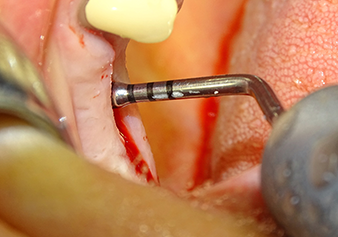

L’insert I2A (diamètre 2,0 mm) est ensuite utilisé pour perforer le plancher sinusien par intermittence et à la plus petite échelle possible. Cette méthode piézochirurgicale spéciale garantit que la membrane de Schneider n’est pas endommagée. Quand le Z25P est utilisé, la membrane est déjà légèrement relevée sous l’effet du fluide de refroidissement délivré via la pointe de l’insert (Fig. 3). Seulement 50 % du fluide de refroidissement sont éjectés afin d'éviter une pression élevée sur le site implantaire.

La membrane de Schneider est soigneusement décollée à l'aide de l’insert Z25P (phase 1).

Fig.3 : Après le marquage de la position de l'implant et l’expansion initiale du site, la membrane de Schneider est soigneusement décollée à l'aide de l’insert Z25P (phase 1).